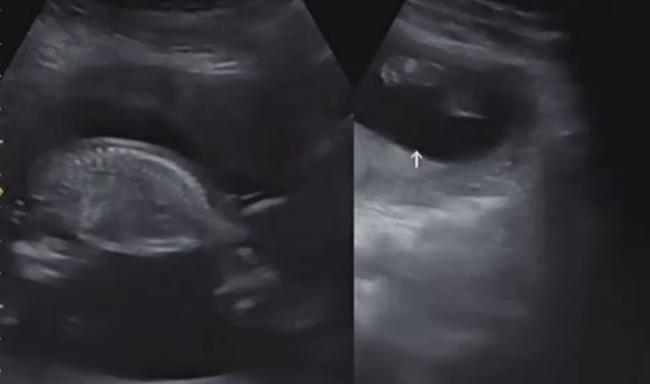

아래 초음파 사진을 한번 보실까요??

(물론 성별이 바뀌는 경우도 많다고 합니다. ㅎㅎ)

* '19.11/20(12주차) 초음파 사진